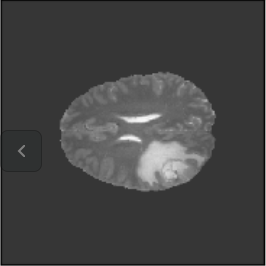

To illustrate the performance of the proposed technique for clinical applications, MR images were chosen. The performance of the technique was tested by registering multi-modal MR image pairs. In a clinical setup, it is common practice to register images or volumes acquired from different imaging modalities or MR sequences. Figure 3 illustrates the degree of overlap between moving images (a) T2 and (f) T1 weighted sequence on fixed images (b) T2 and (g) T2 weighted sequence respectively. It was observed using the registration proposed in this manuscript, the dice score improved from 0.44 (prior to registration) to 0.91 (post registration) for multimodal sequences. On the BraTs data, figure 4 (a-d) illustrates the performance of our method based on other metrics such as Dice, SSMI, MI, and MSE respectively. As the key points were generated by utilizing only the feature maps of the initial two layer of the network, the spatial dimension of the data has little impact on the performance. Unlike other CNN based technique which considers the entire image for estimating the transformation parameters, our method requires CoMs which reduces the dimensionality from (m n n) to (m 2), where m denotes the number of feature maps and n is the pixel dimension of the feature map. This aids in lowering execution time drastically. The proposed pipeline also consists of an uncertainty estimator. uncertainty maps illustrated in all the above examples show the region of higher variance in registration, which in turn suggests surgeons/ observers to make better decisions. Pixel region with red color indicates the larger variance region while blue indicated low variance region. For example in figure 3 (e) shows that the central region of the brain has higher pixel-wise variance as compared to the outer part of the brain. The performance of the algorithm on volumes on the same modality is illustrated in figure 3 (a-e)